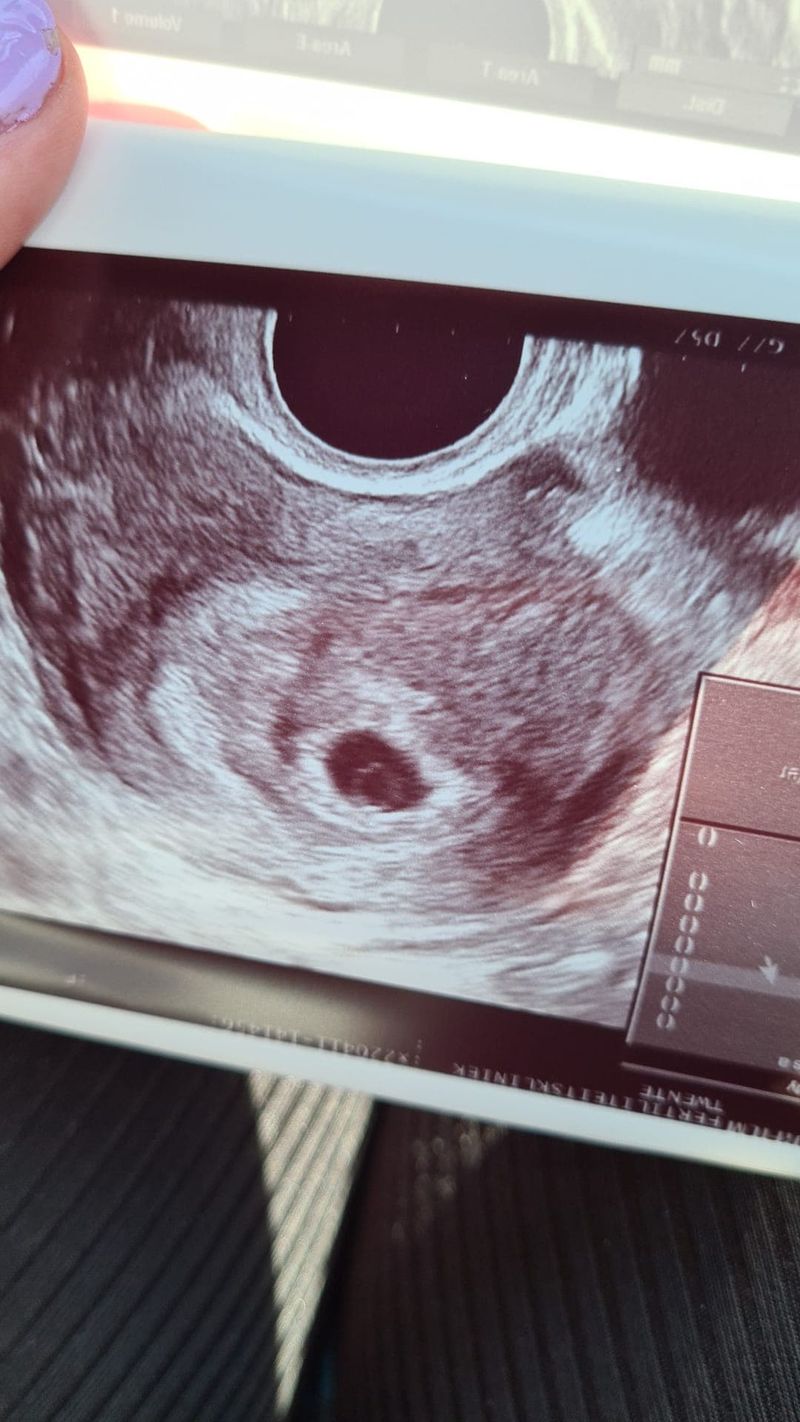

Gelukkig waren er genoeg mensen om ons heen, waar we altijd even ons hart konden luchten. En ook doordat ik op mijn werk zo open was, was dat fijn. Een groot nadeel als je zo open bent was wel dat mensen letterlijk aan je vragen: ”En, wanneer mag je testen?”. Deze dag verschoof ik wel altijd een paar dagen. Al vond ik dit gek, dit vraag je toch ook niet aan een stel dat op een natuurlijk manier bezig is om zwanger te worden? Maar toen het eenmaal gelukt was, vond ik dit erg moeilijk. Ik kreeg echt het gevoel van laat mij even, ik heb het vertrouwen nog niet eens dat het goed mag gaan. En wil ook even met de mensen dicht om ons heen hiervan proberen te genieten.